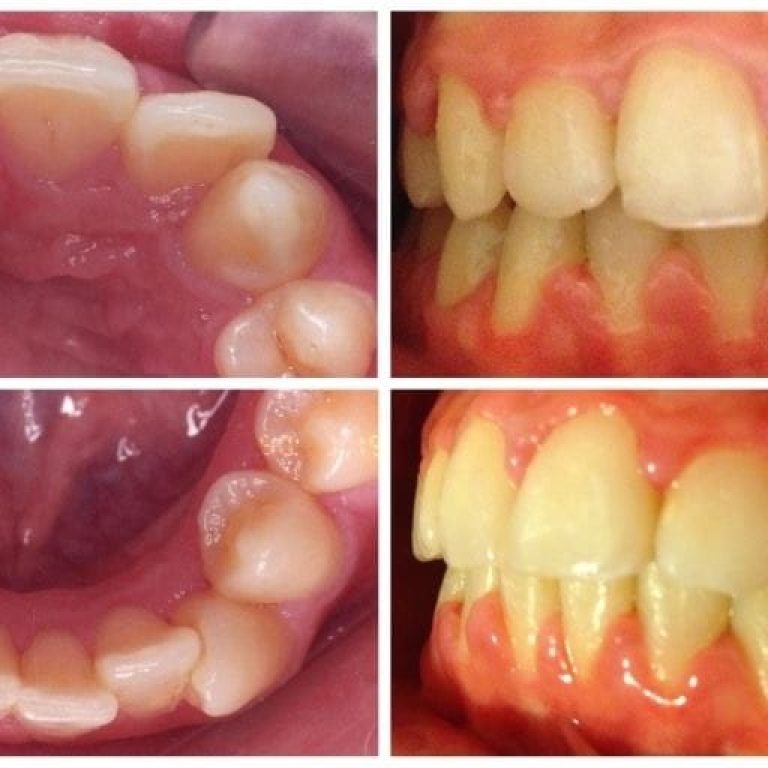

Malocluzia reprezinta o aliniere incorecta a dintilor in momentul muscaturii. In mod ideal, dintii de pe arcada superioara …